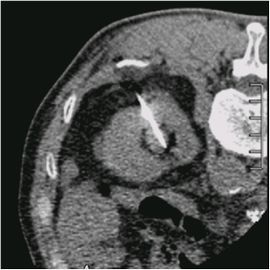

[腎盂がん(左)] 手術:左腎尿管全摘術

CTガイド下針生検